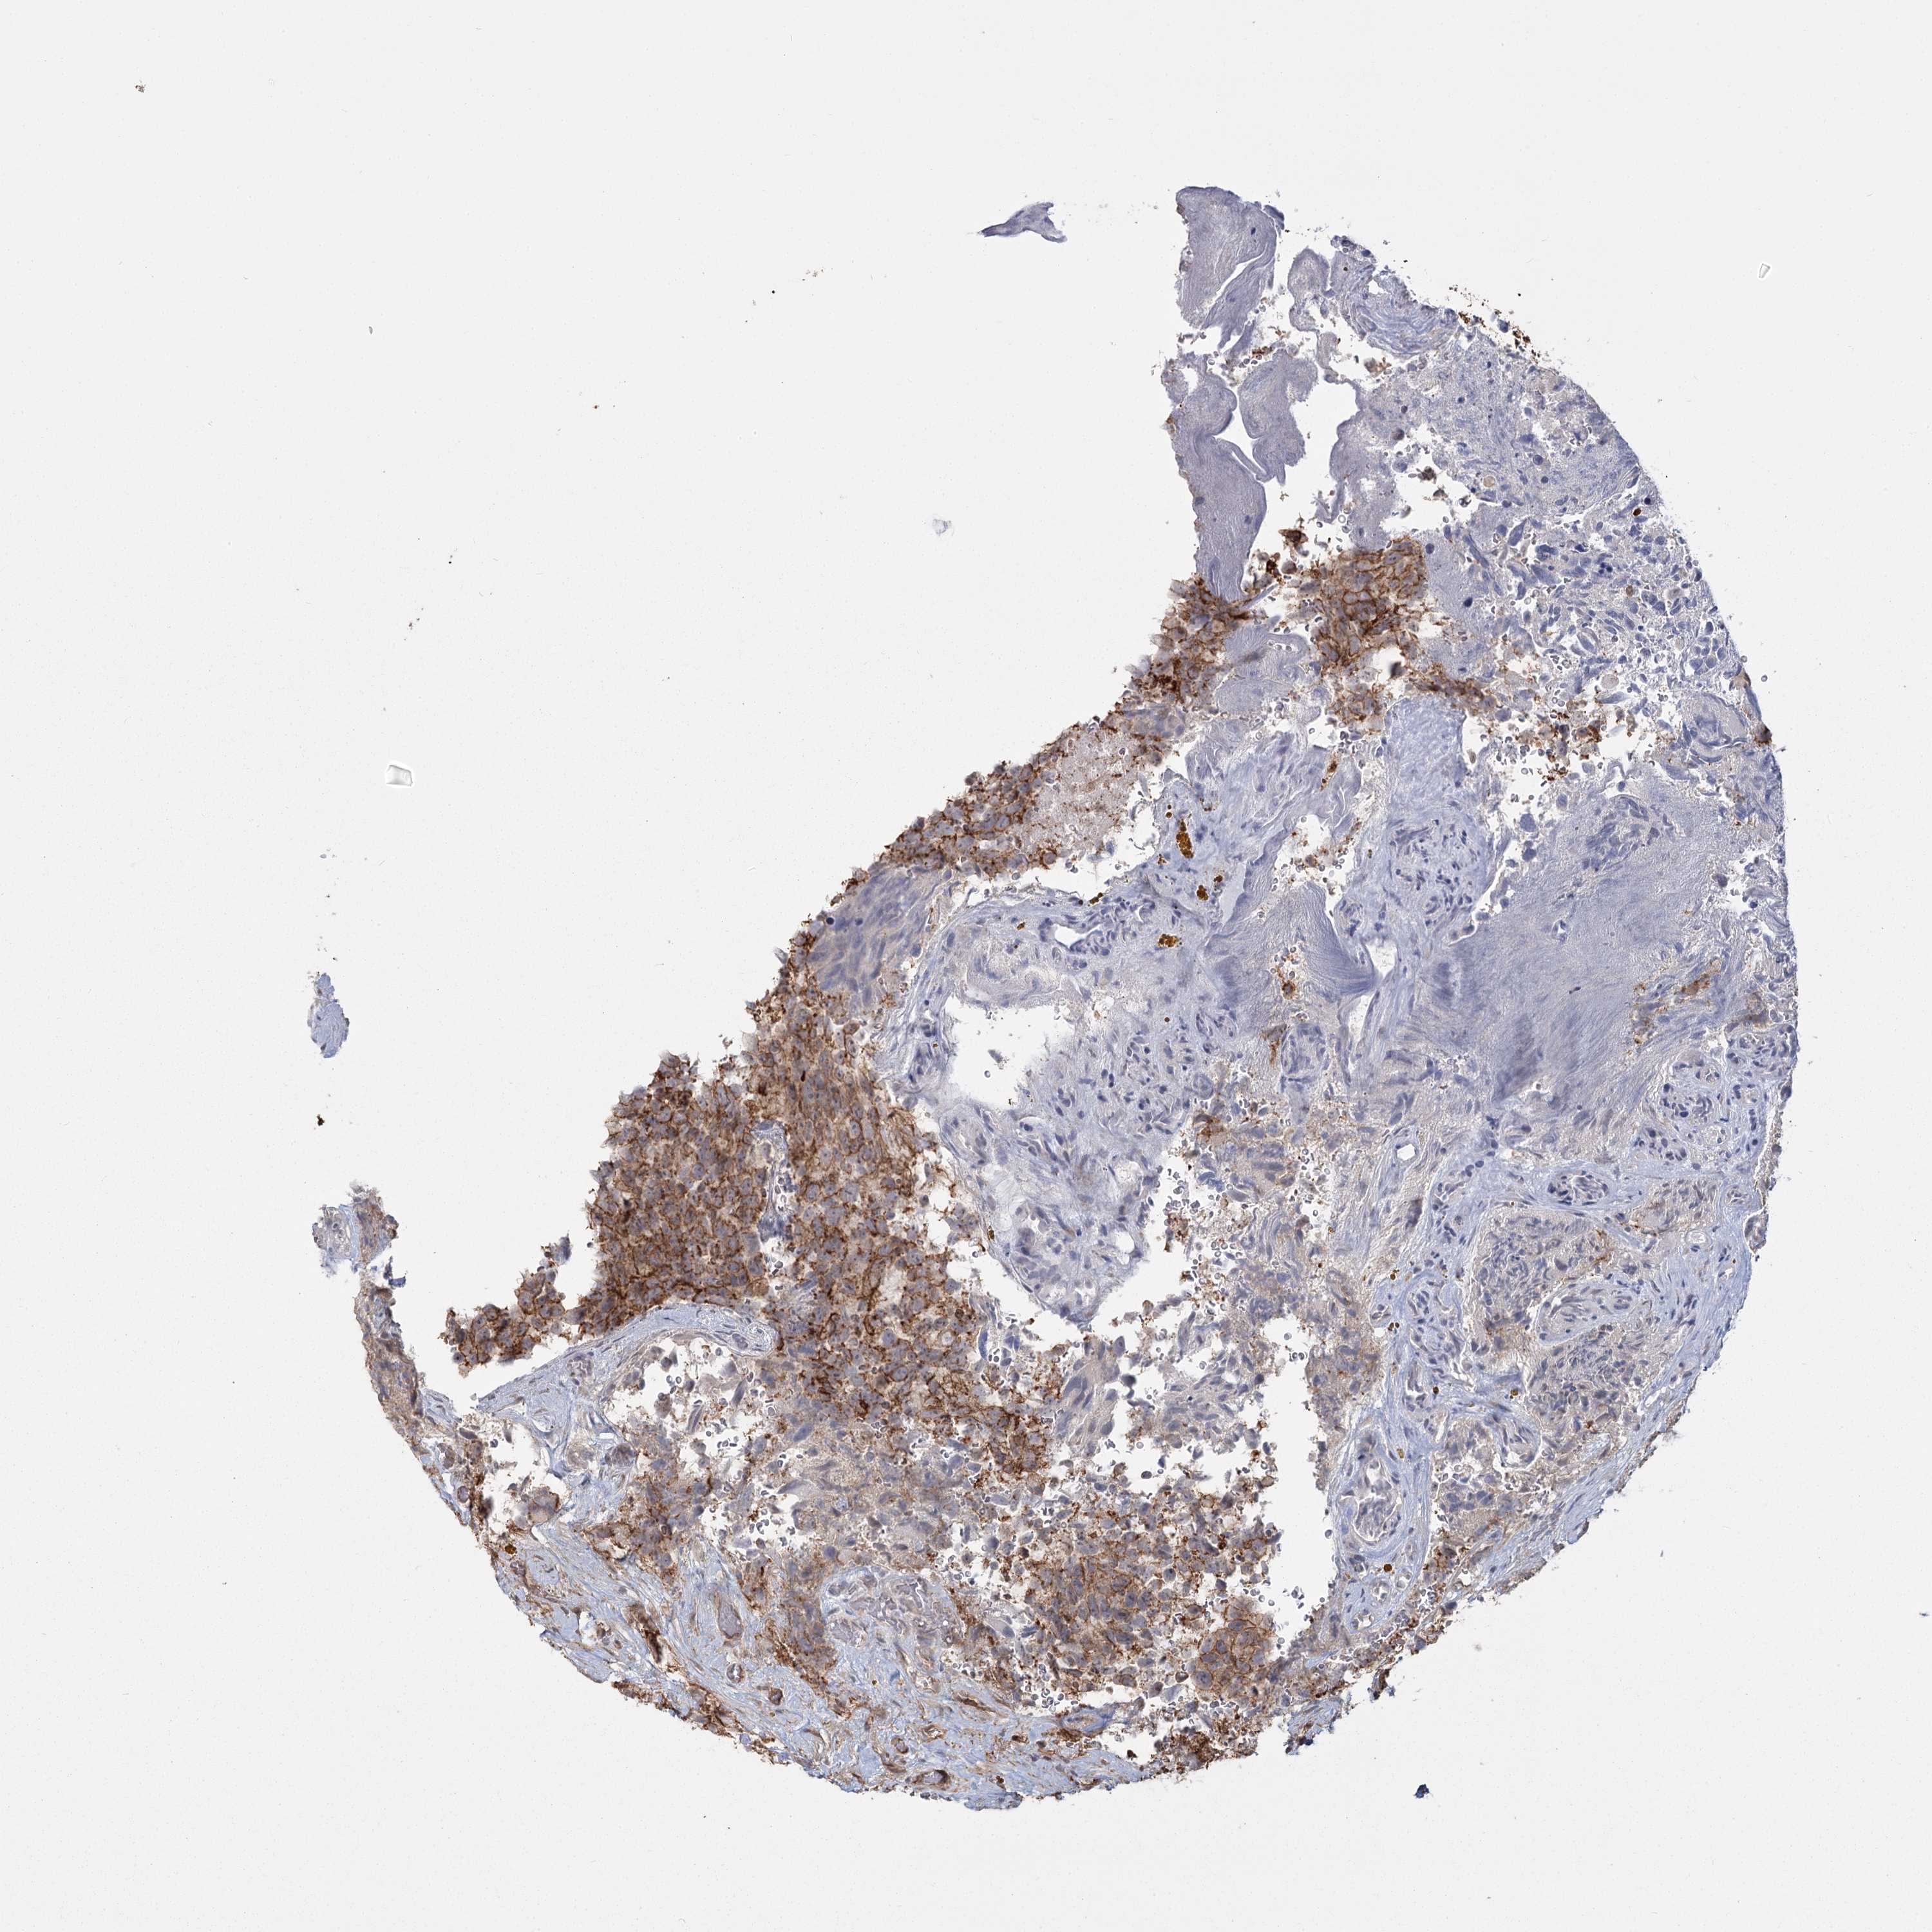

GLIOMA - Protein expressioni

A mouse-over function shows sample information and annotation data. Click on an image to view it in a full screen mode. Samples can be filtered based on level of antibody staining by selecting one or several of the following categories: high, medium, low and not detected. The assay and annotation is described here.

Note that samples used for immunohistochemistry by the Human Protein Atlas do not correspond to samples in the TCGA dataset.

Antibody stainingi

Antibody staining in the annotated cell types in the current human tissue is reported as not detected, low, medium, or high, based on conventional immunohistochemistry profiling in selected tissues. This score is based on the combination of the staining intensity and fraction of stained cells.

Each image is clickable and will lead to virtual microscopy that enables deeper exploration of all samples and also displays staining intensity scores, fraction scores and subcellular localization as well as patient and tissue information for each sample.

Antibody HPA036194

Staining

High

Medium

Low

Not detected

Intensity

Strong

Moderate

Weak

Negative

Quantity

>75%

75%-25%

<25%

None

Location

Nuclear

Cytoplasmic/membranous

Cytoplasmic/membranous,nuclear

Glioma, malignant, High grade